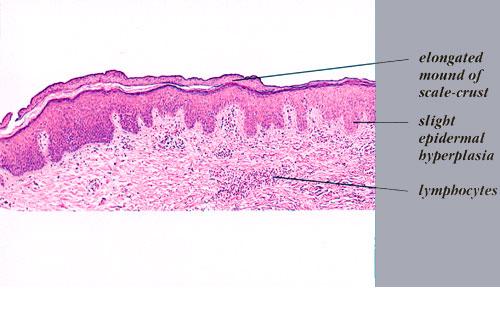

Graft versus Host Disease =داء رفض الطعم للمضيف Graft Versus Host Disease GVHD occurs in situations in which donor immunocompetent T cells transferred into allogenic hosts are incapable of rejecting them. The sources of the T cells include primarily peripheral blood stem cell and bone marrow transplants and, infrequently, unirradiated blood products , solid organ […]